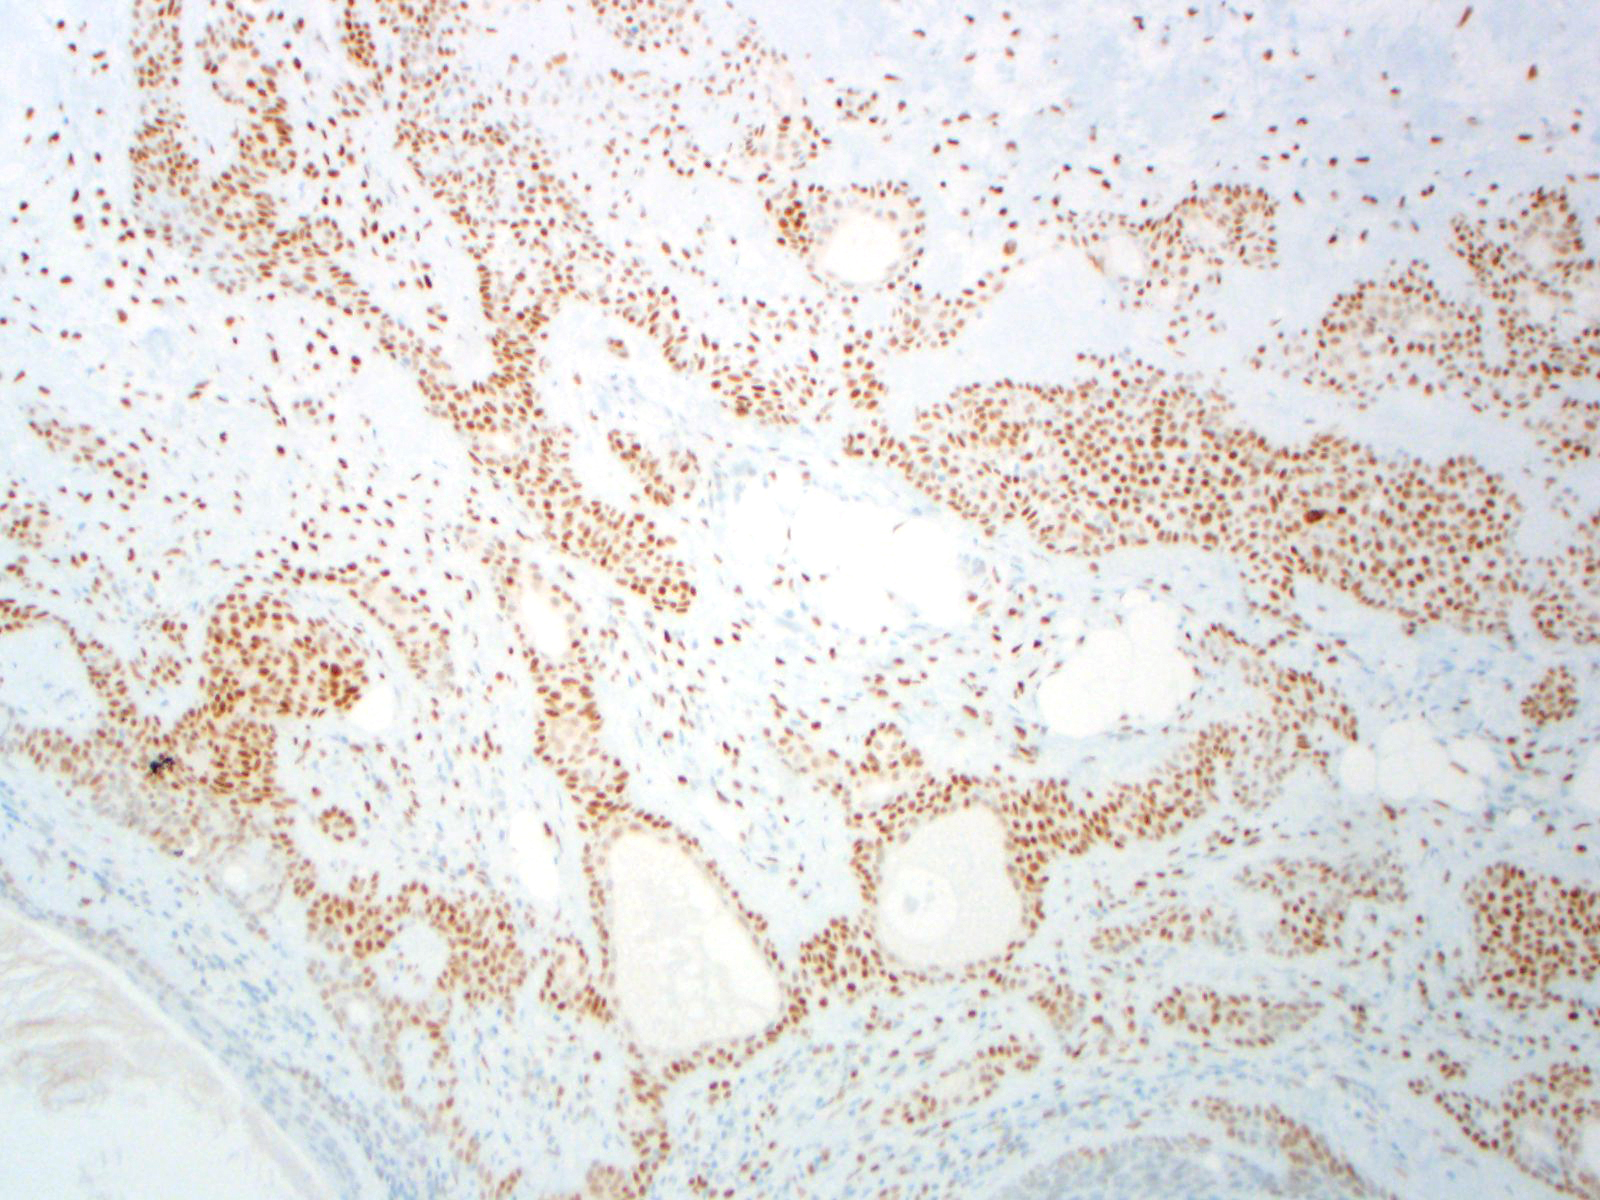

| 2SC |

S-(2-succino)-cysteine |

Rabbit polyclonal (Cambridge Research Biochemicals)

Hereditary leiomyomatosis and renal cell carcinoma (HLRCC) syndrome-associated RCC and leiomyoma

Most renal tumors and leiomyomas not associated with HLRCC

Staining Pattern

Cytoplasmic and nuclear

| HLRCC-associated leiomyoma |